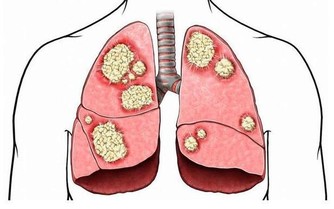

6.唇色泛青:血液不流暢,易患急性病,特別是血管性病變,如血管栓塞、中風等急暴之症。

7.唇色發黑:唇色黯黑,多為消化系統有病,如便秘、腹瀉、下腹脹痛、頭痛、失眠、食慾不振等;

若唇上出現黑色斑塊,口唇邊有色素沉著,常見於慢性腎上腺皮質功能減退。